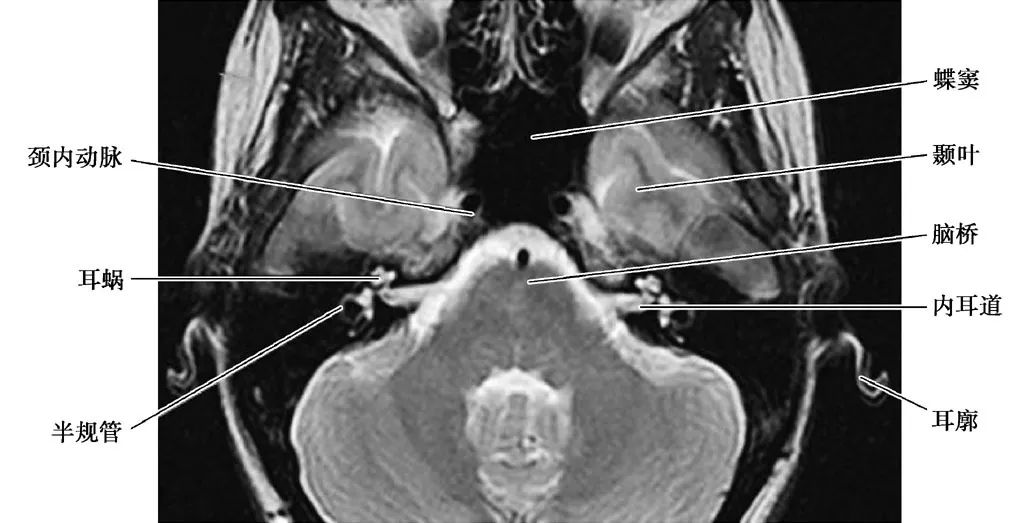

耳部及其周围的重要解剖结构 (CT横断面)

A.上骨半规管层面;B.外骨半规管层面;C.前庭窗层面;D.耳蜗层面;E.颈动脉管层面1.上骨半规管;2.弓形下窝;3.总骨脚;4.后骨半规管;5.外骨半规管;6.内耳道;7.耳蜗;8.面神经管迷路段;9.膝状神经节;10.前庭;11.上鼓室;12.乳突窦入口;13.乳突窦;14.鼓膜张肌;15.锤骨头;16.砧骨体;17.前庭窗;18.前庭导水管;19.圆窗;20.鼓岬;21.锤骨颈;22.砧骨长脚;23.面神经隐窝;24.锥隆起;25.鼓室窦;26.颈动脉管;27.咽鼓管;28.耳蜗导水管;29.颈静脉球

(MRI横断面)